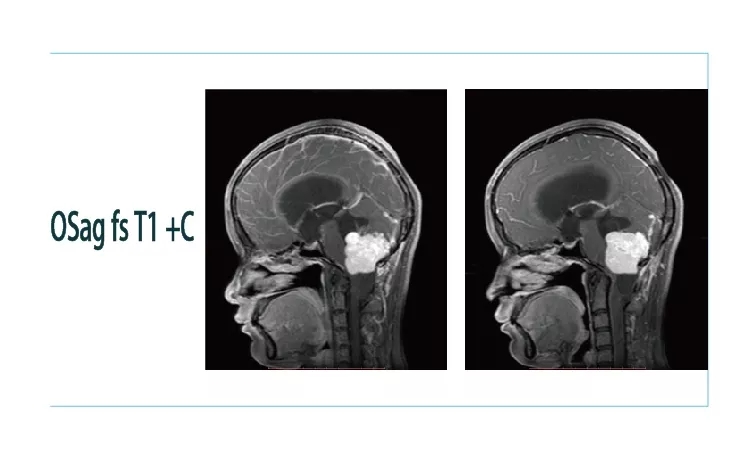

【朗润影像档案】20181026磁共振影像病例结果讨论